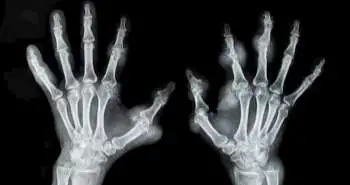

Decrease in bone mineral density during three months after diagnosis of early rheumatoid arthritis measured by digital X-ray radiogrammetry predicts radiographic joint damage after one year

To assess whether the drop in BMD of the hands (BMD loss), as defined by DXR 3 months after diagnosis, anticipate radiographic joint damage following one and two years within patients with early RA.

Digital X-ray radiogrammetry (DXR) is computerised analysis technique to estimate peripheral bone mineral density (BMD). Literuture reports that previous DXR-BMD studies have been based on 12-month change, and by that time, conventional X-ray assessments of joint damage are at least as informative about disease progression. This study reports the DXR-BMD loss during the initial 3 months independently predicted radiographic joint damage at 1 year in patients with early RA.

A total of 167 of these individuals with RA were incorporated in the analysis. Medicine was prescribed under Swedish guidelines, and then a follow up of 2 years was done. Antibodies and rheumatoid factor to cyclic citrullinated peptides were estimated at baseline, and 28-joint Disease Activity Score (DAS28) was evaluated at every visit. Feet and hands radiographs were taken at baseline, three months (hands only), one and two years. The Larsen score assessed baseline and 1-year and 2-year radiographs. Radiographic progression was determined as a difference in Larsen score over the least detectable change. DXR-BMD was estimated at baseline and following three months. The 0.25 and 2.5 mg/cm2/month decline in BMD exhibited a moderate BMD loss and declined up to 2.5 mg/cm2/month described as a severe BMD loss. Multivariate regression was implemented to test the relationship within DXR-BMD loss and radiographic destruction, involving adjustments for possible confounders.

In total, 15% of patients showed severe, and 44% showed moderate DXR-BMD loss at the initial three months. Out of these patients, 19% exhibited radiographic progression at one year and 35% at two years. During multiple regression analyses, a significant relationship was seen between DXR-BMD loss and increase in Larsen score between baseline and one year.

DXR-BMD loss at the first three months autonomously estimated the radiographic joint destruction at one year among individuals with early RA. Thus, DXR-BMD may be a beneficial tool to identify ongoing joint damage and thereby to enhance individualisation of treatment during early RA.